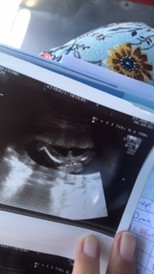

ลูกสาวชัดๆ คุณแม่แอบลุ้นลูกชาย มีโอกาสจะมีจู๋โผล่ออกมาไหมค่ะ ลูกสาว 2 แต่ก้อรักสุดค่ะ

บ้านนี้ผู้ชายจ้าา อ้าให้เเม่กับป้าหมอดูกันชัดๆ555

มาชัดเลยค่ะแม่ ว่าเป็นลูกสาว😊